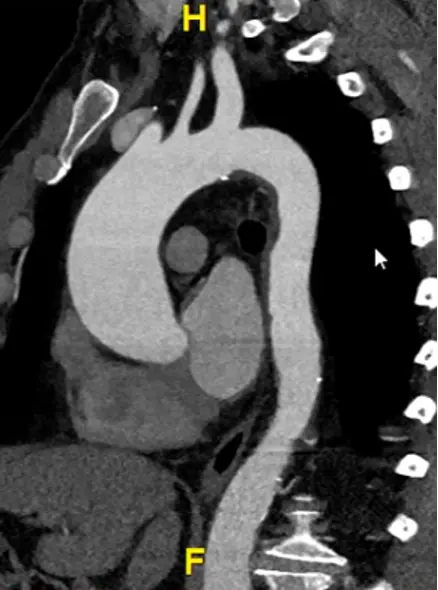

- Start at the sinuses of Valsalva

- Hit

Xto grab your cross-hairs. You will drag the cross hairs to the middle of the sinuses of Valsalva in the axial view window. - In your coronal view window, there is a pink/red line with a small circle. Drag this circle to line up the pink/red line to be perpendicular to the wall of the sinus of Valsalva. The blue/purple line should be in the center of the long-axis of the aorta at the sinus of Valsalva.

- Similarly for your sagittal view, you will want your pink/red line to be perpendicular to the sinuses of Valsalva. You will also want your green line to be in the center of the long-axis of the aorta at the sinus of Valsalva.

- Once youâve lined things up, in your axial view window you will now have what is called a âtrue short axisâ of the aorta at that level.

- Slide up and down to evaluate the AV anatomy. You will be able to determine if it is tricuspid, bicuspid, etc.

- Recall, the RCC is going to be the most anterior cusp. HINT: There is an âAâ (for anterior) at the top of the axial window and a âPâ (for posterior) at the bottom to help orient you.

Measure at sinuses of Valsalva

- Measure aortic root diameter at the sinuses of Valsalva on CT

- Drag the lines until you see the widest section in the coronal and sagittal planes